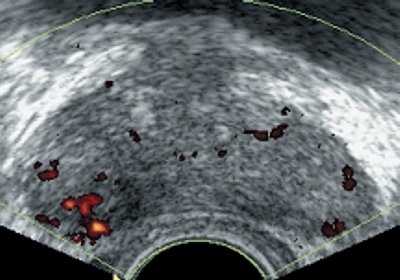

При анализе результатов ТРУЗИ в режиме серой шкалы нельзя было однозначно трактовать фокальные изменения как злокачественные или доброкачественные. Гипоэхогенные участки, расположенные в периферической зоне, дифференцировали с простатитом, а участки в переходной зоне - с узлами доброкачественной гиперплазии предстательной железы. Поэтому во всех случаях в выявленных гипоэхогенных участках исследовали кровоток с помощью энергетического картирования и 3D-реконструкции сосудов. Использование 3D-реконструкции сосудов в режиме энергетического допплеровского картирования позволяет получить более богатую и насыщенную сосудами картину, чем при обычном двухмерном исследовании, и легче выявить зоны асимметрии васкуляризации. У всех пациентов при раке предстательной железы определялись патологически измененные сосуды в зоне гипоэхогенных участков опухоли (рис.4), которые в отличие от неизмененных сосудов были извиты, прерывисты, имели различный калибр, хаотично располагались в зоне опухоли. Степень васкуляризации опухоли была различной - от гиповаскулярной до гиперваскулярной.

Рис. 4. Патологические изменения в сосудах при раке предстательной железы, асимметрия васкуляризации долей в режиме энергетического картирования и с применением 3D-реконструкции.

а) Энергетическое картирование (в случае подкапсульной опухоли).

б) Энергетическое картирование + 3D реконструкция (в случае подкапсульной опухоли).

в) Энергетическое картирование (при прорастании капсулы).

г) Энергетическое картирование + 3D реконструкция (при прорастании капсулы).

В наших наблюдениях у 20 больных раком предстательной железы при двухмерном энергетическом картировании усиление васкуляризации гипоэхогенного участка отчетливо диагностировалось у 6 пациентов, а при 3D-реконструкции сосудов в режиме энергетического картирования у 10. У всех пациентов с раком предстательной железы при 3D-ангиографии определялась асимметрия васкуляризации.